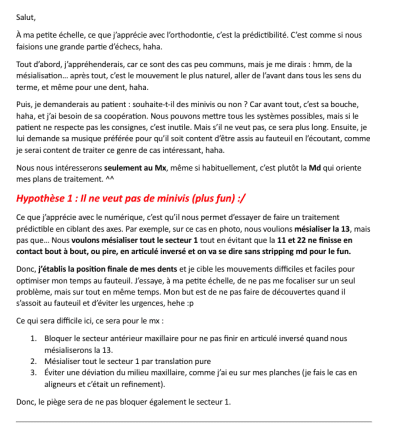

Les deux cas sont présentés ci-dessous après fermeture des diastèmes. Est-ce que vous percevez la difficulté du second ?

Que proposez-vous ?

suite : la voilà (cas 2) avant et après (à parfaire avec une seconde phase de coronoplasties) .